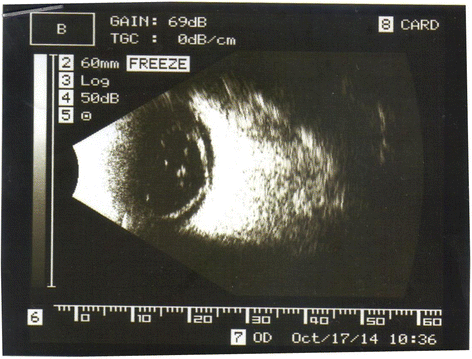

A 39-year-old woman was brought to the emergency center at Şevket Yılmaz Training and Research Hospital as she had a low-voltage household electrical injury. When the patient was brought to the emergency room, she had developed a cardiac arrest. She was intubated and placed under treatment in the intensive care unit. She lost consciousness for 1 week following the accident. At the time of admission, she had third-degree burns on the right side of her leg. An ocular examination given in the course of admission revealed normal findings without any corneal or lenticular opacity and evidence of penetration or perforation of the globes. Apart from those findings, no symptoms of electrical burns were observed on either of the eyelids and around the eyes. During the four weeks of hospitalization, the patient suffered from a gradual worsening of vision in the right eye. Her vision in right eye was limited to perception of hand motions, with an intraocular pressure of 13 mmHg in each eye. In her right eye, a slit-lamp examination showed non-granulomatous anterior uveitis with nuclear cataract (Fig. 1). Fundus examination could not be carried out on the right eye. An ultrasound examination also showed total retinal detachment (Fig. 2). The patient reported normal visual acuity in each eye before the injury. There were no pathological findings in the left eye. There were no systemic or methabolic changes which may cause cataract. The patient was treated with topical dexametazon and %1 siklopentolat HCL ophthalmic solution four times daily and she was referred to another center for vitreoretinal and cataract surgery. After cataract surgery combined to pars plana vitrectomy with gas tamponade the patient’s postoperative Snellen visual acuity at first month visit was 0.2.